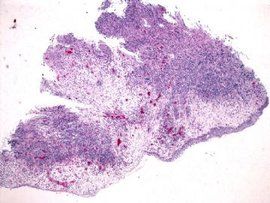

F、嗜酸性淋巴肉芽腫:病變累及汪表淋巴結,青壯年多見,表現為肋部、眼部、頸部、上臂、腹部腫塊,有一組或多組淋巴結腫大,皮膚瘙癢、乾燥、局部色素沉著。白細胞總數正常或稍增加,也可正常,嗜酸粒占0.10-.077,淋巴結穿刺或活檢示大量嗜酸粒細胞浸潤。